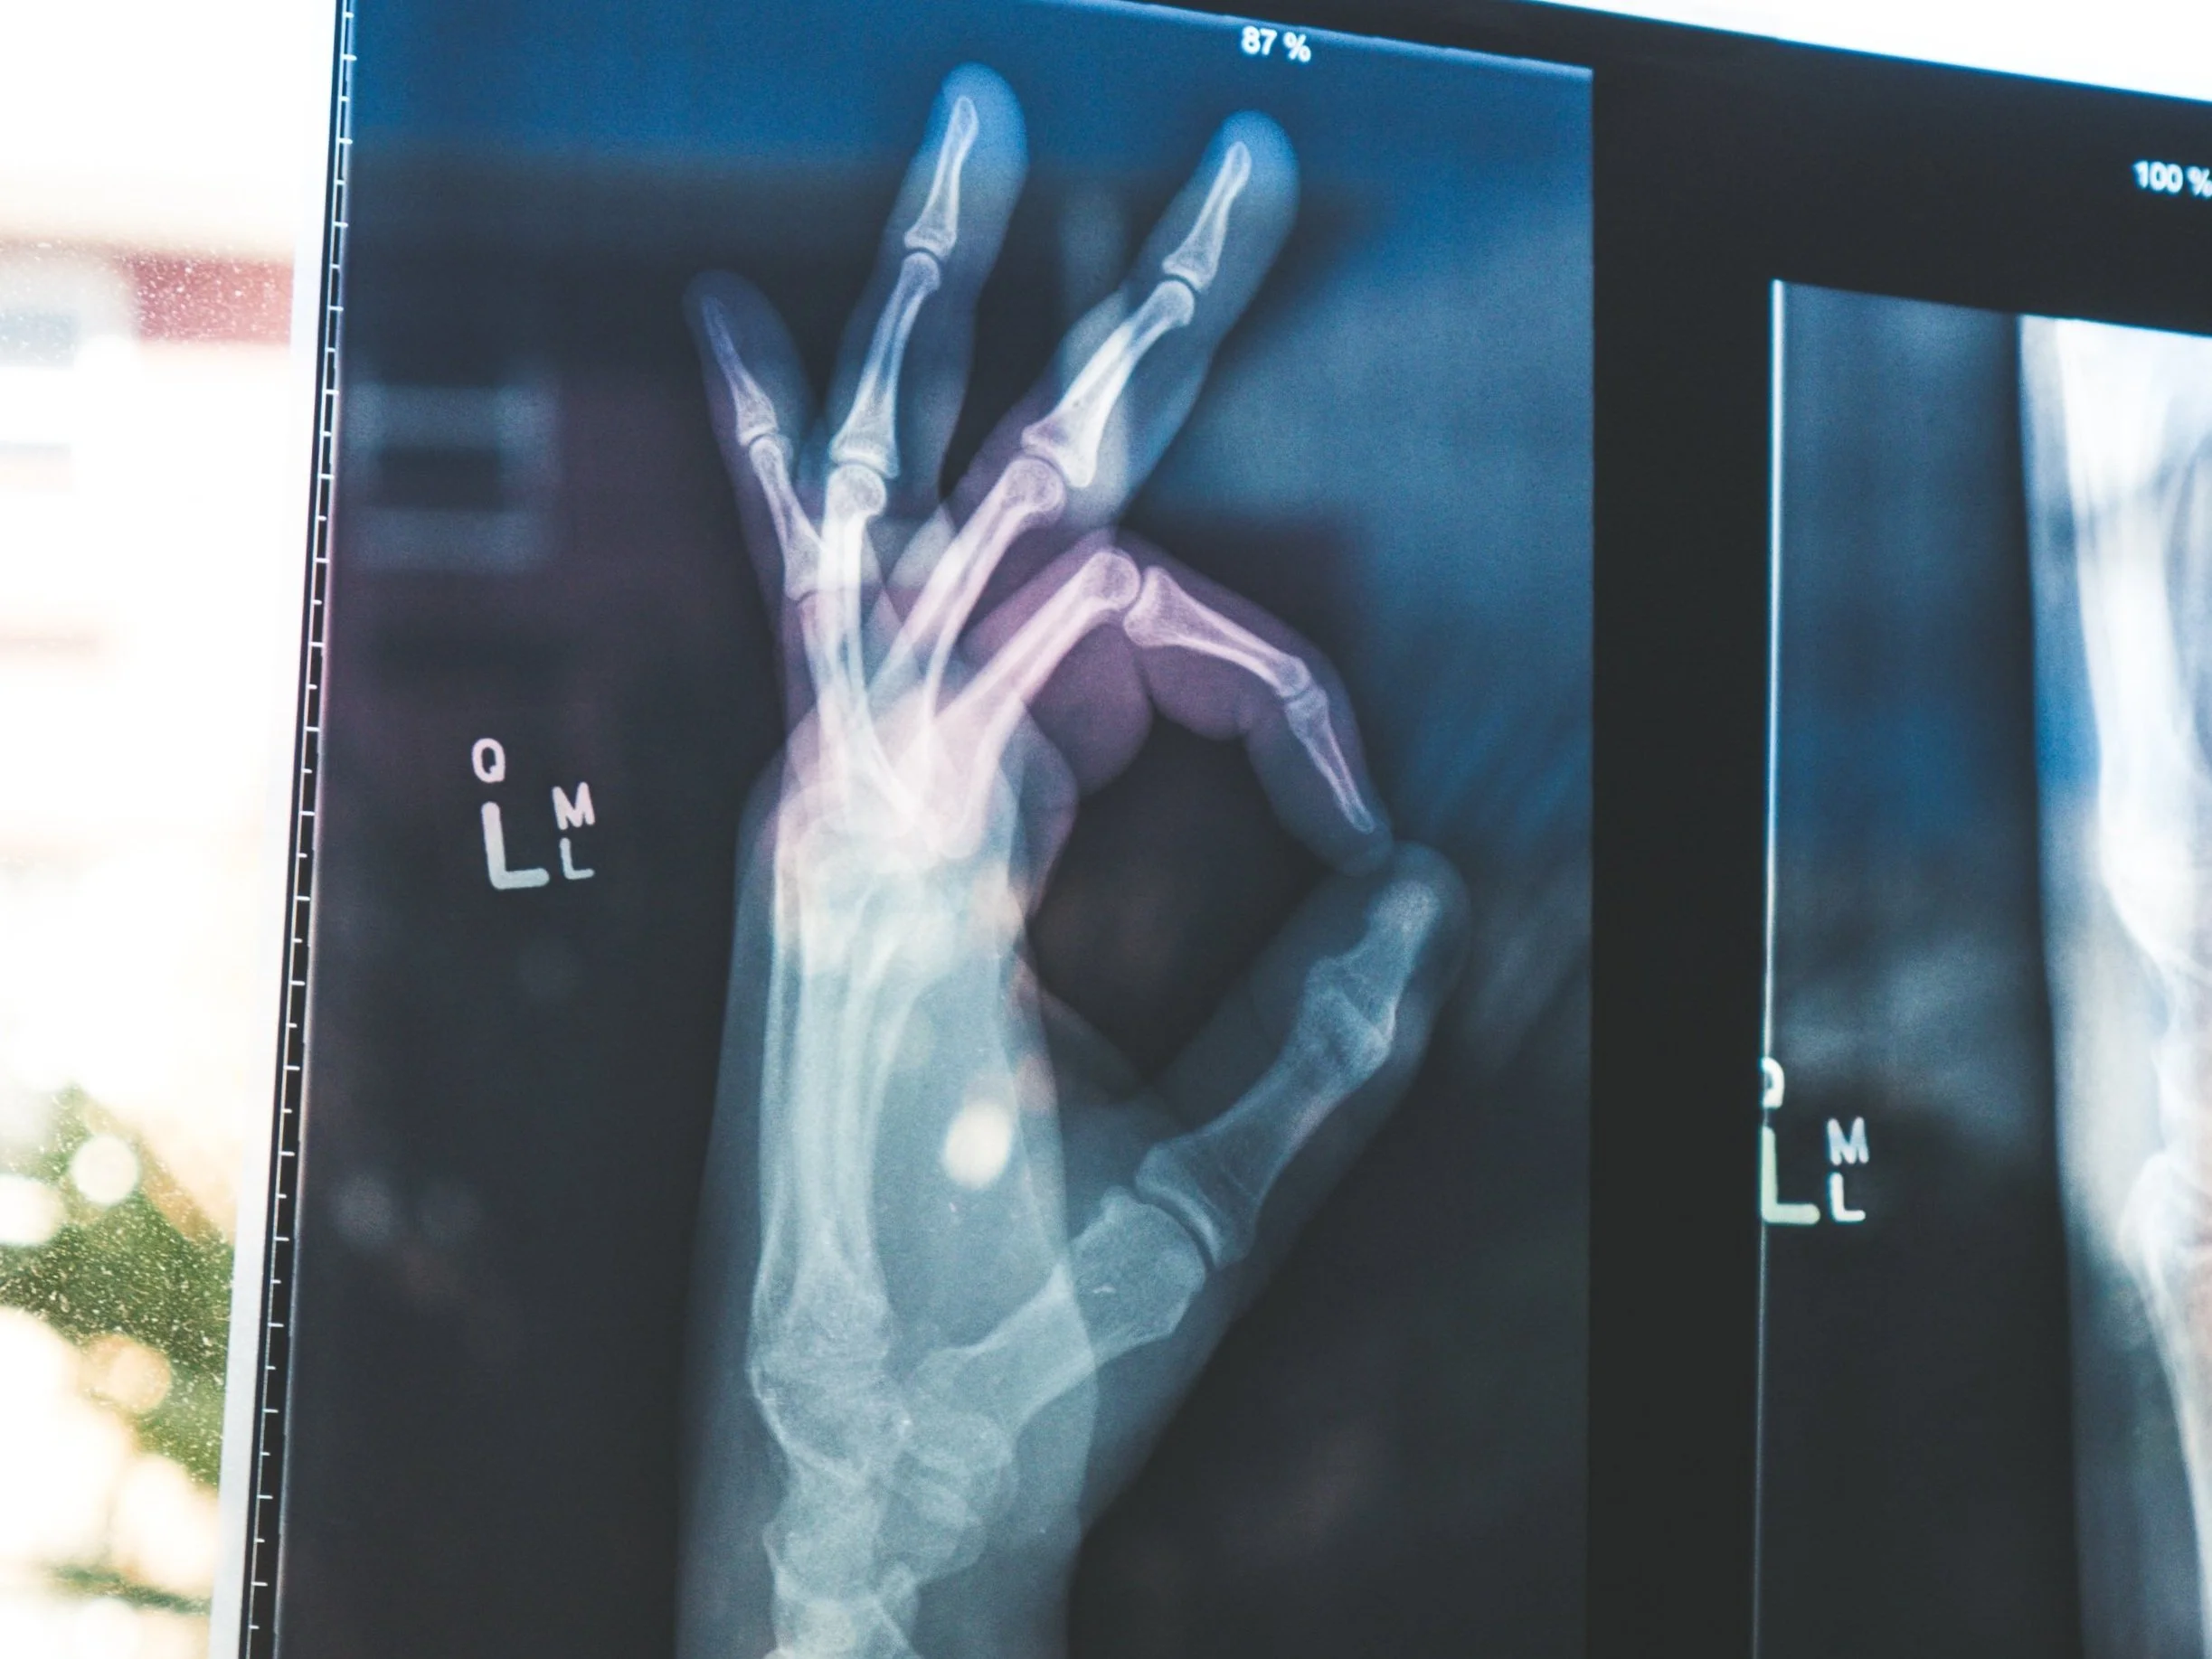

Sim! A diferenciação entre osteopenia e osteoporose é feita pela densitometria óssea, que é um exame parecido com radiografia (raios-x) e que serve para aferir/medir a massa óssea. Porém esse exame, embora fundamental, não é capaz de avaliar apropriadamente a porção proteica da estrutura óssea.